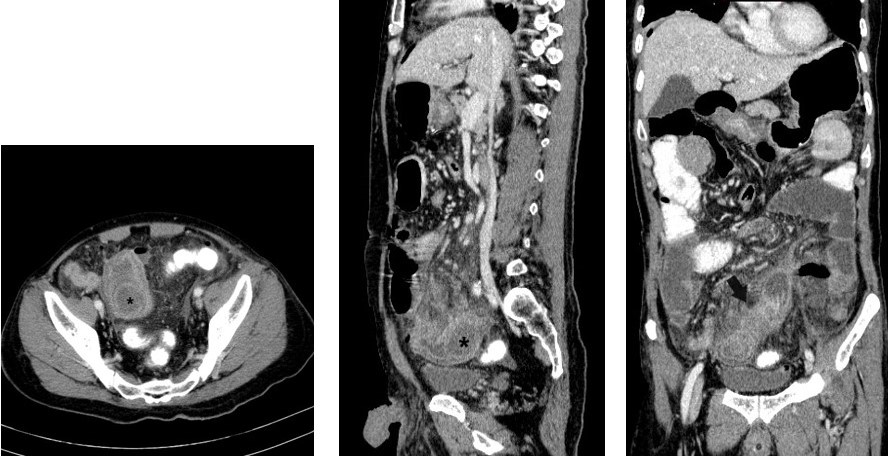

Neurofibromatosis (NF) is a genetic neurological disorder which can lead to abnormal tumour suppression. Neurofibromatosis associated neurological tumour is usually benign in nature, only occasionally can become malignant. Gastrointestinal involvement is reported to be infrequent with only up to 25% of patients with neurofibromatosis showing involvement. Solitary gastrointestinal neurofibroma is very rare, with most cases involving the stomach or small bowel. We report here a case of solitary small intestinal neurofibroma with no other associated systemic signs, causing intussusception and intestinal obstruction.